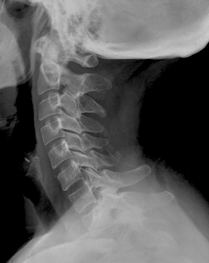

Columna Cervical Lateral

Paciente de pie o sentado, con la cabeza en posición neutra. El haz de rayos es dirigido horizontalmente al centro de la vértebra C4 (a nivel del borde inferior de la mandibula). Si el paciente está en decubito, el cassette se ubica lateral al cuello, con el haz de rayos dirigido horizontalmente 2,5 a 3 cm bajo la apofisis mastoides